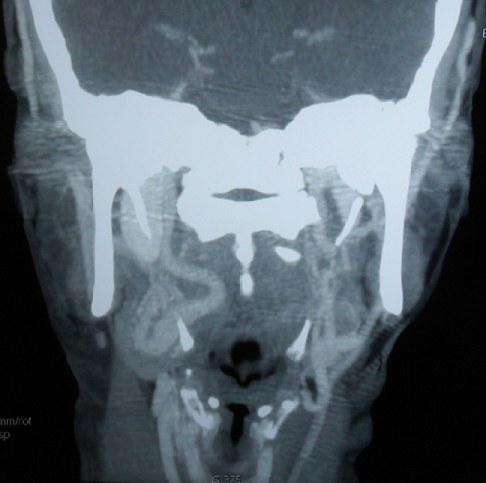

L'artère carotide interne aberrante est une malformation congénitale rare. Les malpositions de cette artère sont bien mises en évidence sur la TDM injectée ou mieux sur l'IRM (avec des séquences angiographiques) qui est considérée l'examen le moins invasif et permettant de confirmer l'anomalie et les rapports de l'artère carotide interne avec les autres structures du pharynx. Par son siège vulnérable, cette artère, au contact direct de la muqueuse de la tonsille palatine, représente un risque fatal lors d'un geste chirurgical même anodin (amygdalectomie, véloplastie, adénoïdectomie) ou un geste invasif de la région pharyngée. Les précautions à prendre avant tout geste chirurgical impose une palpation systématique de la région pharyngée. Toute asymétrie oropharyngée doit inciter à demander une imagerie. Patiente âgée de 55 ans, sans antécédents pathologiques particuliers, a consulté pour une odynophagie sans fièvre ni altération de l'état général. L'examen physique a objectivé un bombement du mur postéro-latéral droit de l'oropharynx refoulant l'amygdale droite, avec une muqueuse normale en regard. Le reste de l'examen était sans anomalies. L'examen biologique n'a pas noté d'anomalies. Plusieurs diagnostics ont été évoqués en particulier un lymphome ou une néoplasie solide. Un scanner cervical injecté a objectivé un trajet aberrant de l'artère carotide interne dans sa portion cervicale, décrivant une boucle sous muqueuse, refoulant le mur postéro-latéral droit de l'oropharynx. Le diagnostic d'un trajet aberrant de l'artère carotide interne a été alors posé.